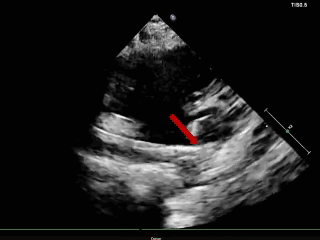

成型锁定

四腔心切面

主动脉短轴切面

封堵器呈“Y”字形牢牢抱住主动脉,夹持缺损